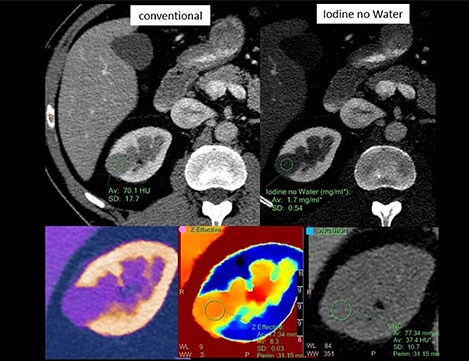

Case study: lesion characterization

The patient in this image was referred for characterization of a lesion in the kidney, suspected to be a kidney cyst when viewed on conventional CT. The cystic lesion is visible in the conventional contrast CT image (top left), but that gives little information about what it is. Switching to a visualization that enhances iodine and suppresses water (top right), the measurement indicates that there is iodine uptake and the lesion is metabolically active. Looking at the effective atomic number (bottom center), it can be seen that the Zeff value is 8.3, well above the value of water. The bottom right image is virtual non-contrast, filtering out all iodine signal and showing just the anatomy of the kidney. All spectral information in this case assisted in confirming this kidney malignancy, with just a single scan. In yet another view it is possible to check the heterogeneity of the lesion. Tumor heterogeneity is used as a guide to create more refined treatment strategies and response to therapy.